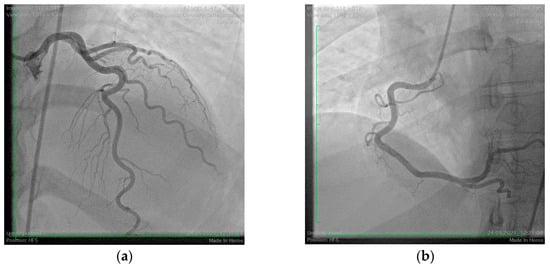

A 43-year-old woman was transferred to our hospital from a Surgical Oncology clinic after experiencing a lateral ST-segment elevation myocardial infarction during anesthesia induction for the treatment of endometrial adenocarcinoma. During induction, the patient developed angioedema, which was promptly treated by the oncology team. She had no known history of allergies and was undergoing hormonal replacement therapy for hypothyroidism. On admission, her hemodynamic and respiratory parameters were stable, with a blood pressure of 100/70 mmHg, heart rate of 78 bpm, and oxygen saturation (SpO2) of 98%. Laboratory findings showed significantly elevated high-sensitivity troponin I levels (6.3 mg/L), leukocytosis (12,400/mm3) with eosinophilia (10.2%), and mildly elevated C-reactive protein (6.4 mg/L), indicative of systemic inflammation. Her lipid profile revealed dyslipidemia with elevated LDL cholesterol (159 mg/dL) and non-HDL cholesterol (171 mg/dL). Echocardiography demonstrated normal left ventricular systolic function (LVEF = 55%) but revealed hypokinesia of the lateral wall. Coronary angiography showed normal coronary arteries, leading to the diagnosis of myocardial infarction with non-obstructive coronary arteries (MINOCA) (Figure 4). The likely etiology was attributed to coronary vasospasm induced by atracurium administration during anesthesia induction. The patient was discharged with a prescription for a low-dose calcium channel blocker to prevent recurrence.

Figure 4. Coronary angiography with non-obstructive coronary arteries. (a) Normal left coronary arteries; (b) normal right coronary artery.